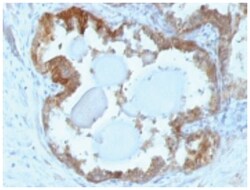

HSP27 Monoclonal specifically detects HSP27 in Human, Mouse, Rat, Chicken, Chimpanzee, Monkey, Sheep samples. It is validated for Western Blot, Flow Cytometry, Immunohistochemistry, Immunocytochemistry/Immunofluorescence, Immunohistochemistry-Paraffin.Specifications

| This MAb reacts specifically with heat shock protein HSP27 in human and monkey tissues and cell lines such as MCF-7. HSP27, also referred to as the Estrogen-Regulated 24K protein and HSP28, is one of several small heat shock proteins produced by all organisms studied. HSP27 synthesis is induced by elevated temperature, as well as by estrogen in hormone responsive cells. Interestingly, human HSP27 also shares greater than 50% homology with low molecular weight Drosophila HSPs and mammalian alpha-crystalline lens protein. Because of the estrogen responsive nature of HSP27, this protein has been studied extensively in human estrogen responsive tissues such as cervix, endometrium and breast tissue. Therefore HSP27 may be useful in classifying various hormone sensitive tumors. |